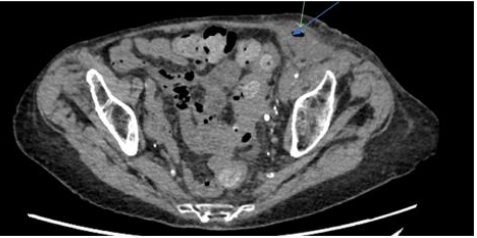

On examination, the abdomen was soft with generalised left-sided tenderness. A firm, tender swelling was palpable in the left inguinal region which was not able to be reduced. Laboratory investigations showed a normal WCC of 9.0x109/L and mildly elevated CRP of 23. CT-abdomen showed appearances suggestive of a left inguinal hernia containing a loop of small bowel, suspicious for an incarcerated hernia (Figure. 3).

Figure 3: Axial view of CT-abdomen/pelvis showing left-sided inguinal hernia with localised perforation

The patient went on to have a laparoscopic exploration of the groin which revealed no hernia. However, a sinus tract with chronic changes communicating with peritoneal cavity was found. Upon further exploration, the sigmoid colon was found to be very inflamed and adherent to the sinus with a hard mass palpable, thought to be colonic diverticulitis. The sigmoid colon was technically difficult to separate from the hernia sac, and during the process a contained perforation sealed off by the hernia sac and omentum was revealed. As it was deemed unsafe to return the sigmoid colon to the abdominal cavity, the decision was made to proceed to a Hartmann’s procedure through a midline laparotomy and a loop colostomy formed. The operation was complicated by necrotising fasciitis of the hernia site resulting in further debridement and significant morbidity.